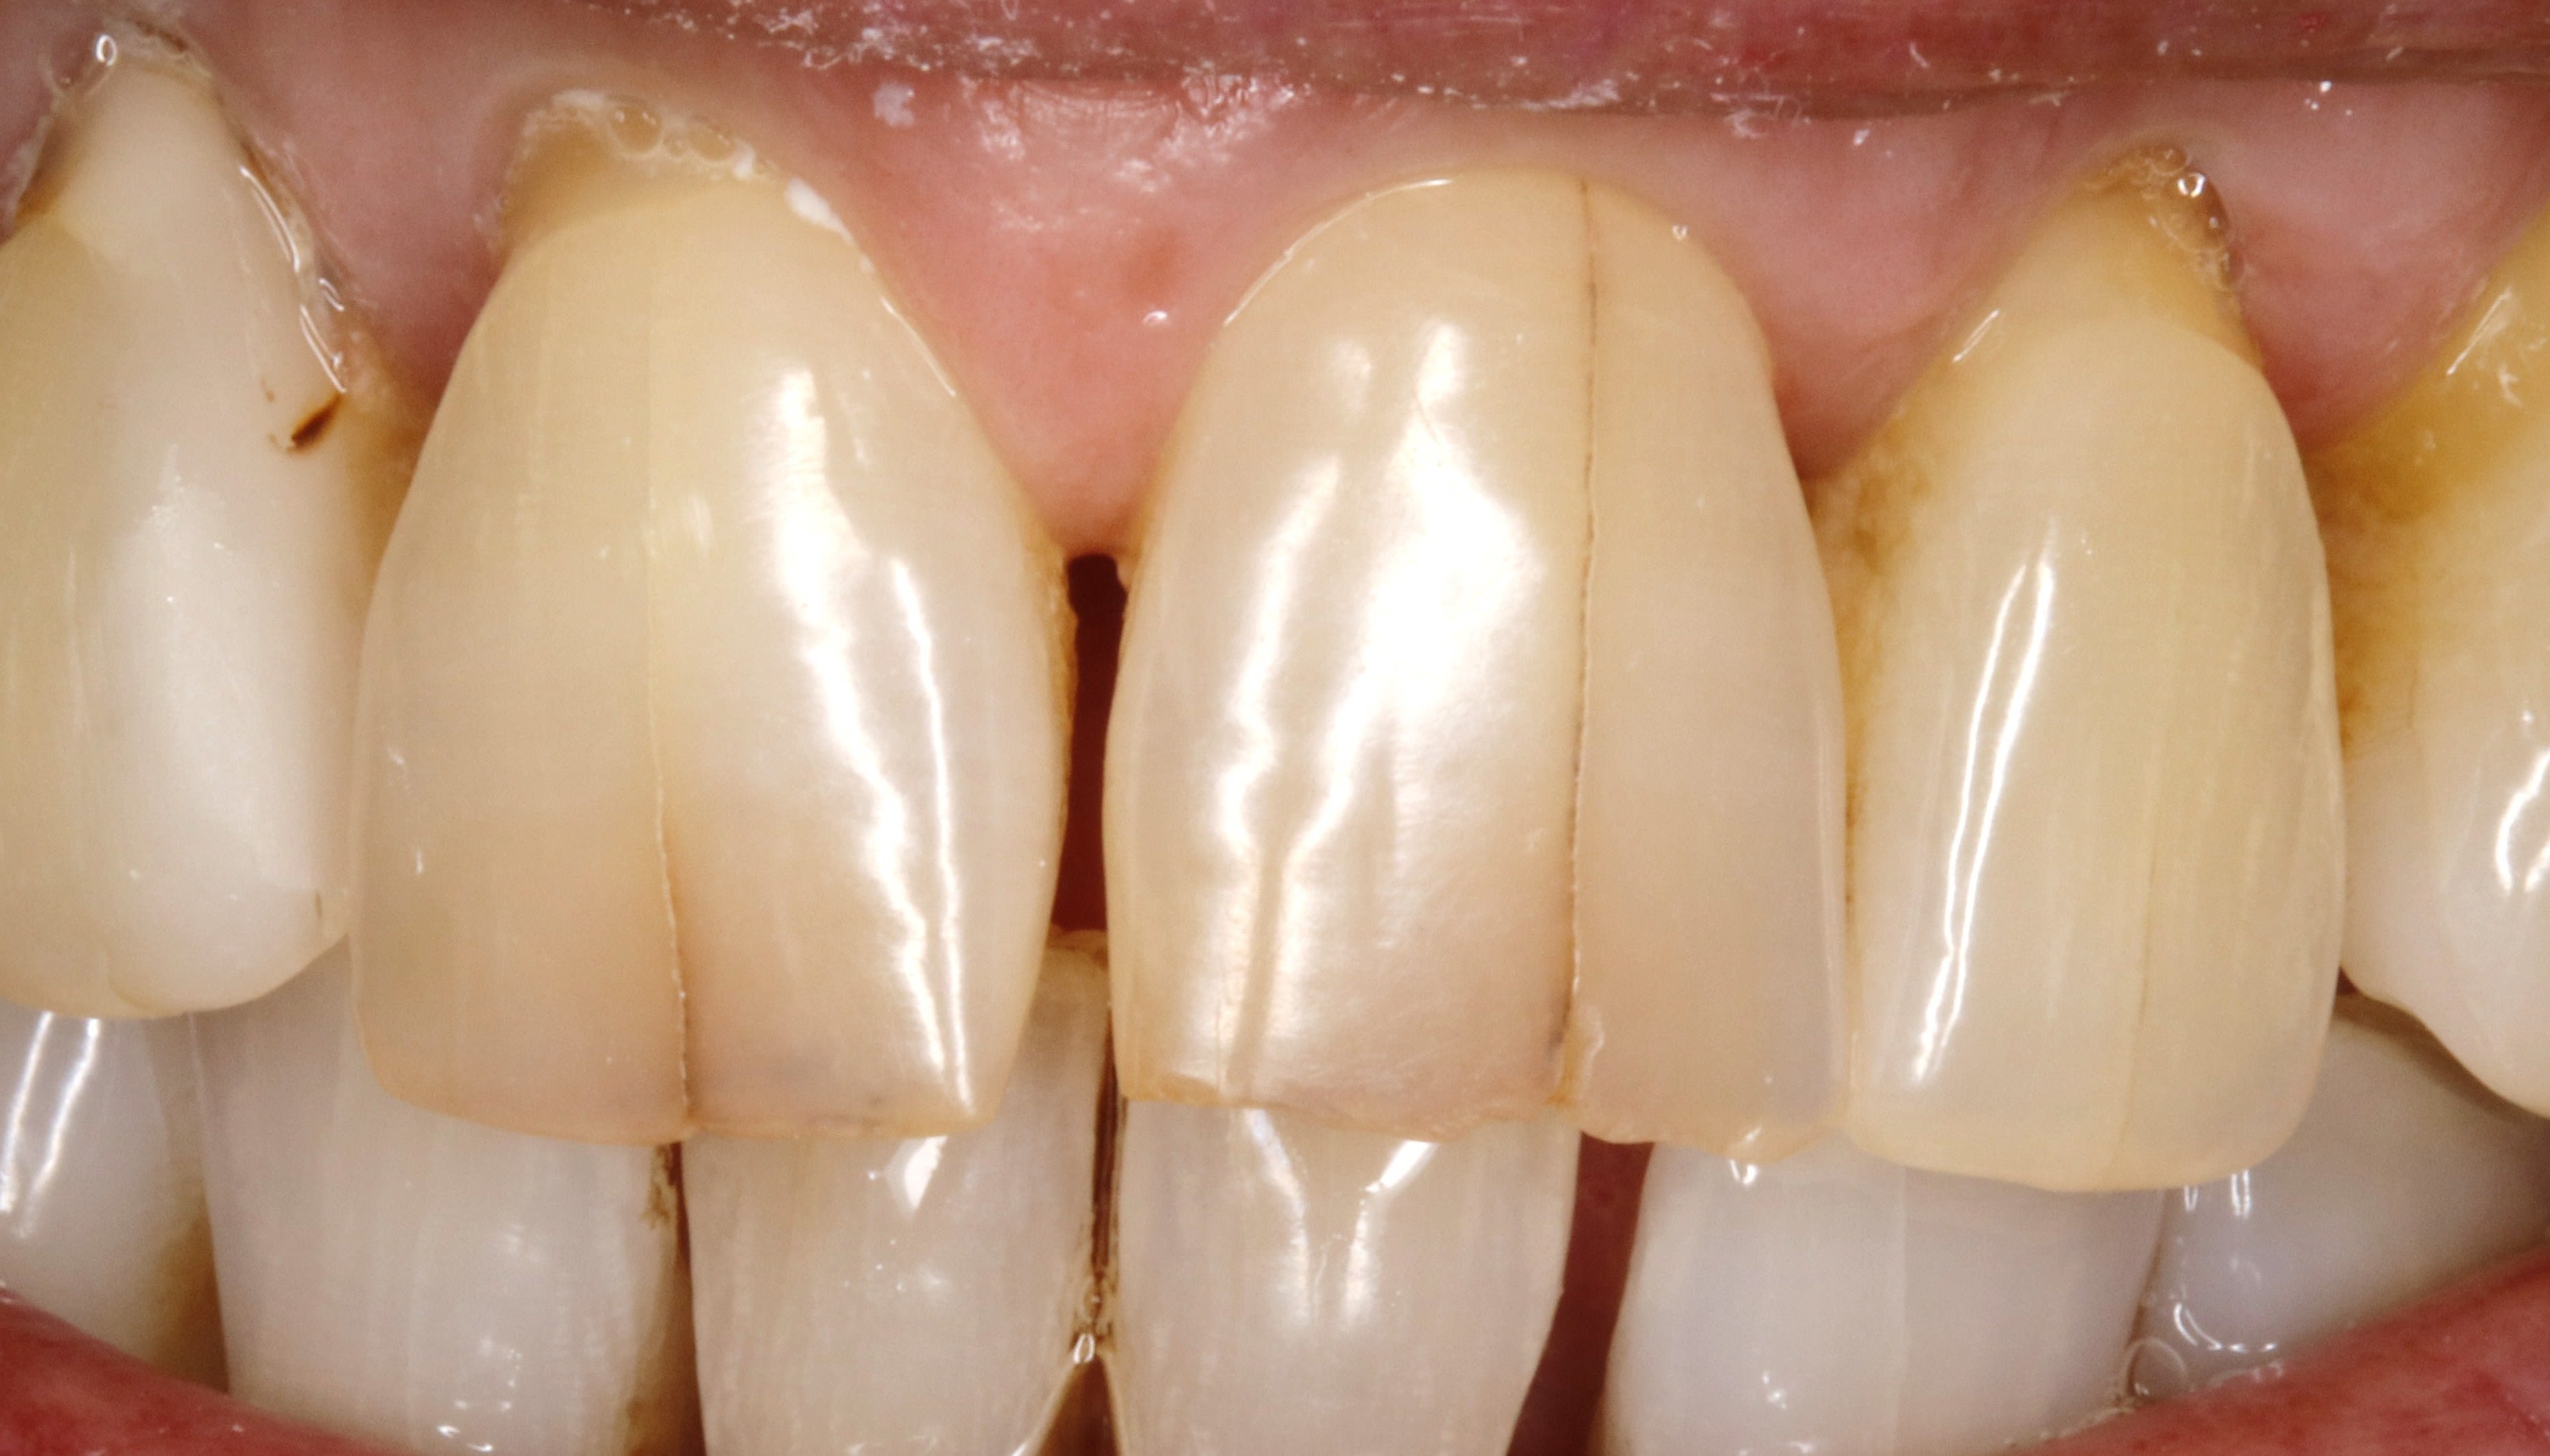

Bon les gars, y a rien là ?

(fait en 2012)

Alors, c'est pas de la déquichisation ça ?

Ai oublié la tof des tailles, pour pas qu'on dise que c'est pas moi qui l'ai fait.

c'est bizarre de rien faire en bas:-)))) surtout une fois (presque) bien en haut.

Ben elle voulait pas d'ortho et faire que le haut et merci pour le presque, enfoiré ;-)